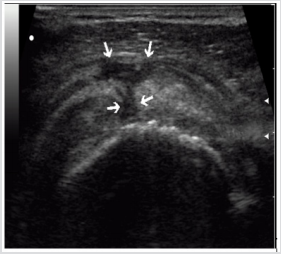

A complete rupture of the rotator cuff against the background of acute in-jury occurred in 64.8% of cases, against the background of chronic injury - in 35.2% of cases, respectively (P <0.05). The absence of tendon imaging in a typical place was detected in 70% of cases, while in the sonogram the humeral head contour was determined (70%) with adjoining the deltoid muscle (70%). Such an echographic picture corresponded to a massive rupture of a rotator cuff with damage to several tendons. In 96% of cases, complete rupture of the rotator cuff of the shoulder was accompanied by effusion in the subdeltoid-subacromial bag, in 90% of cases the effusion had a heterogeneous structure with hyperechoic inclusions, indicating the organization of the hematoma. In 57% of cases with identified effusion in the wall of the sub-deltoid-subacromial bag there was an increase in vascularization (Figures 1-4).

Figure 1: Echogram of complete rupture of the rotator cuff. There is no imaging of the tendons in a typical place, the contour of the humeral head is bare, the deltoid muscle is adjacent to it is visualized.